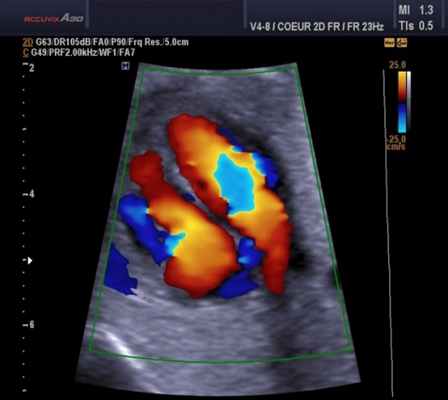

Техническая справка: Эхокардиография с допплерометрией и ЦДК

Эхокардиография с допплерометрией и цветным допплеровским картированием (ЦДК) – это сочетание обычного двумерного ультразвукового сканирования сердца для анализа его анатомии с допплерометрией. Эффектом Допплера называется физическое явление изменения частоты ультразвука при отражении его от движущихся объектов. Допплерометрия позволяет оценить ток крови, его направление, скорость и характер, а в сердце выявить недостаточность и стеноз клапанов, отрывы хорды и т.д. Сочетание обычного двумерного серошкального УЗИ с допплерометрией плюс добавление цветовой кодировки потоков крови (от УЗ-датчика и к нему) – это цветное допплеровское картирование. С его помощью наши специалисты сразу видят патологические забросы крови (из полости левого желудочка во время систолы в левое предсердие при недостаточности митрального клапана).

Для облегчения выявления турбулентного движения (завихрений) существует порог скорости, выше которого происходит изменение цвета (во многих аппаратах это зелены). «Мозаичный» узор на участке турбулентного потока позволяет легко установить регургитацию (смену направления движения), что помогает определить степень недостаточности клапанов.